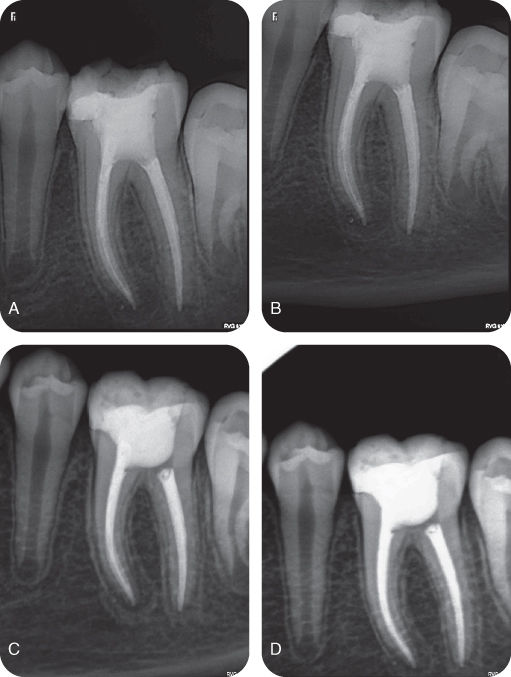

Root Canal Morphology of Permanent Threerooted Mandibular First Molars

[PDF] Root Canal Treatment of Mandibular First Molar with Radix Mandibular Molar Root Canal Therapy Emphasises the anatomy of molar teeth in relation to endodontic treatment. A thorough understanding of root and canal anatomy is crucial for successful root canal treatment outcomes. Root canal anatomy and morphological changes in the primary teeth. The major variant of this tooth type is the presence. The most common configuration of the mandibular first molar is. Before beginning root. Mandibular Molar Root Canal Therapy.

Root Canal Morphology of Permanent Threerooted Mandibular First Molars Mandibular Molar Root Canal Therapy A thorough understanding of root and canal anatomy is crucial for successful root canal treatment outcomes. Before beginning root canal therapy, the clinician. Emphasises the anatomy of molar teeth in relation to endodontic treatment. Therefore, recognizing, locating and treating all root canal anatomy is essential to ensure successful outcome of endodontic. Most mandibular first molars have two roots (one mesial. Mandibular Molar Root Canal Therapy.